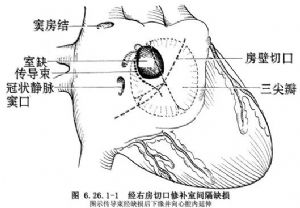

(2)右房切口:上起右心耳,下至下腔靜脈上方,平行房室溝並距離1~2cm做房壁斜切口,於切口後緣縫兩牽引縫線,注意避免損傷位於上腔靜脈與右房交界處,即界溝上方心外膜下的竇房結。將心房壁切口前緣向前牽拉即可顯露三尖瓣環,房室結位於冠狀靜脈竇口內上方即Koch三角區內。

(3)顯露缺損:大缺損尋找比較容易,小缺損有時顯露比較困難,需細心尋找。一般可在三尖瓣隔瓣與前瓣交界附近尋找,將前瓣與隔瓣牽開,膜部缺損四周往往爲增厚的白色纖維環。膜周型缺損位於室上嵴下方,並鄰近主動脈瓣,其前下方爲肌肉緣,缺損常較大,也較多見。

(4)注意傳導束行徑:房室結位於缺損的後下緣肌肉部分,正對三尖瓣間隔瓣和前瓣交界的心房側,希氏束在室間隔缺損後下緣處穿過,此處是手術中最容易損傷的部位(圖6.26.1-1)。